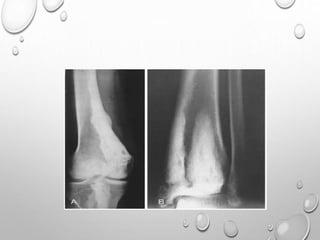

LL >> UL

SHORT STATURE WITH TENDENCY TOWARDS DWARFISM

BILATERAL SYMMETRICAL INVOLVEMENT

DEVELOPMENT OF EPIPHYSES DELAYED

APPEARANCE IS MOTTLED WITH IRREGULAR MINERALIZATION

FLATTENED AND SQUARED-OFF EPIPHYSES

DOUBLE LAYERED PATELLA……PATHOGNMONIC

HYPOPLASTIC TIBIAL AND FEMORAL CONDYLES WITH SHALLOW

INTERCONDYLAR NOTCH

METAPHYSES ARE FLARED

CARPALS , TARSALS AND LONG TUBULAR BONES OF HAND ,SOMETIMES

FEET ARE SHORT AND THICK

SPINE : ANTERIOR WEDGING , SCOLIOSIS

IRREGULAR EPIPHYSES LEADS TO PREMATURE AND SEVERE

DEGENERATIVE CHANGE ESPECIALLY IN KNEES AND HIPS.